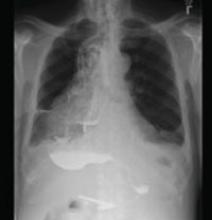

A 20-year-old black man came into our medical center with a mildly pruritic scaly rash affecting his neck and upper body for 2 weeks. Physical exam revealed well-demarcated, hyperpigmented hyperkeratotic papules coalescing to form large plaques on his central chest, back, and shoulders. He had a reticulated pattern on his shoulders and arms (FIGURE 1). His face, intertriginous skin, genitals, mucous membranes, and lower extremities were spared. The remainder of the physical exam was unremarkable.

Woods lamp and potassium hydroxide (KOH) preparation were negative. Labs, including fasting blood glucose and thyroid function test, were normal. Our patient denied any recent travel, fever, night sweats, or weight loss. He noted only that he used the weight benches at the gym. His medical and family histories were unremarkable, and he was not taking any medications or supplements.

FIGURE 1

Plaques on chest, reticulated pattern on arms

Dx: Confluent and reticulated papillomatosis

Confluent and reticulated papillomatosis of Gougerot and Carteaud (CRP) is a rare skin disorder characterized by benign blue-gray or brown hyperpigmented hyperkeratotic papules and plaques. The lesions initially occur on the trunk or central chest as 1- to 2-mm warty papules that become confluent to form plaques, spreading to the neck, abdomen, and upper extremities. Peripherally, the lesions are distributed in a reticular pattern. Although less common, CRP may be isolated to one part of the body, including the face and genitals; the mucous membranes are swpared.